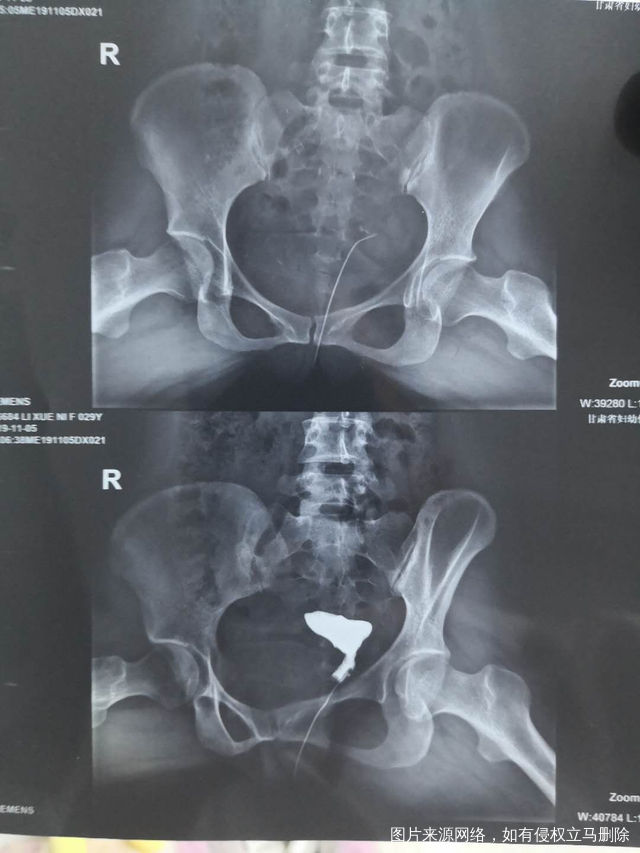

做完输卵管造影第六天了小腹还是感觉沉甸甸的如

可以热敷腹部,如果有发热,腹痛加剧,白带量多,有异味,随时就医